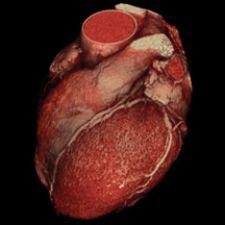

Barco just received FDA 510(k) clearance for CardiaMetrix, its clinical application suite for structural and functional analysis of contrast-enhanced cardiac studies. Integrated into PACS with Voxar 3D and VesselMetrix, a clinical application for quantitative vessel analysis of CTA and MRA, CardiaMetrix’s segmentation and bone removal software is designed to allow users to extract small vessels quickly and provides a 4-D cardiac analysis tool to produce 4-D movies of the beating heart with cardiac contours. The 4-D cine rapidly generates short axis, two-, three- and four-chamber long axis views, semi-automatic alignment with cardiac long axis position and automatic transfer of long axis position in end-diastolic and systolic phases to cardiac (LV) analysis.

TeraRecon recently upgraded Aquarius Workstation version 3.5, which offers protocol-based workflow tools that automatically present the 3-D volume data set based on the study type selected by the operator. For cardiovascular CT for example, the software offers new soft plaque analysis, automatic vessel segmentation and extraction, measurement, interpretation and reporting tools. For CT colonography, the entire colon is automatically segmented upon loading with flight paths automatically generated, enabling the user to switch from 2-D synchronized views to 3-D fly-through mode.